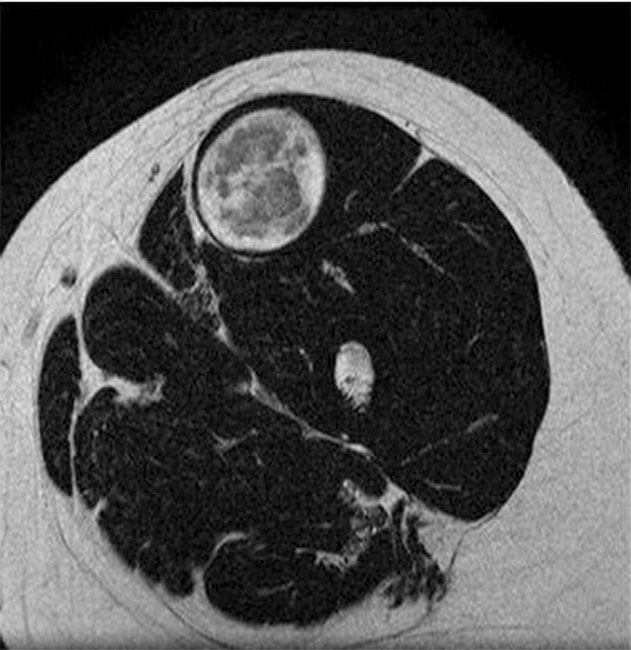

Resonancia magnética en ponderación T2 de muslo izquierdo en corte axial, muestra una lesión de bordes definidos con centro hipointenso y un halo hiperintenso (target sign).